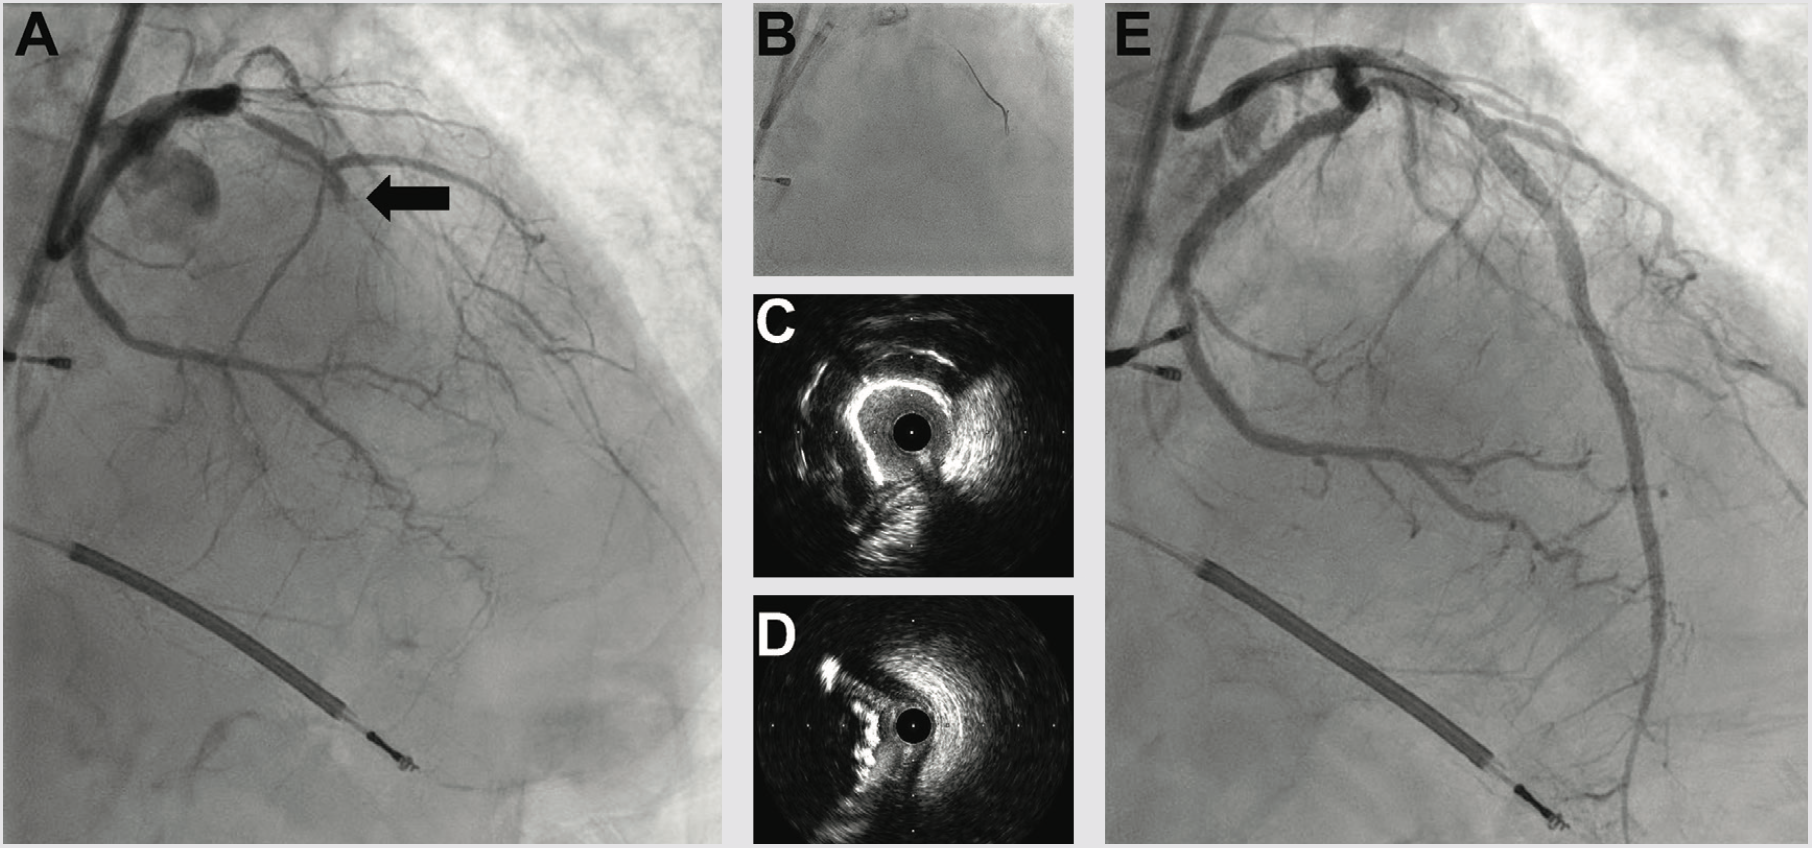

Three weeks later, we performed LAD CTO PCI. The LVEF had improved to 35%, and the patient was euvolemic and hemodynamically well compensated. Right radial occlusion and left radial vasospasm prevented 7 Fr radial access, so we re-accessed the LCFA, where angiography showed a widely patent iliac Shockwave treatment zone from the prior case. Using a 7 Fr system, diagnostic angiography demonstrated patency of the LCX, LPDA, and OM1 treatment sites. We next utilized an AWE strategy to address the LAD CTO (Figure 4). CTO wires immediately tracked subintimal and using a Mongo wire, we used mini-subintimal tracking and antegrade reentry (STAR) to reenter the LAD with <20 mm subintimal distance (Figure 4). Initial noncompliant balloons would not expand completely. IVUS showed (1) severe circumferential and nodular calcium in the proximal and mid LAD, and (2) limited (<20 mm) subintimal tracking before luminal reentry. We treated with a 3.5 mm Shockwave balloon to modify the calcium compliance to facilitate optimal stent expansion. After additional predilation with 1-to-1 sized noncompliant balloons, we placed overlapping stents, post dilated under IVUS guidance, and achieved excellent IVUS and angiographic results (Figure 4). The patient was discharged the following day, and on follow-up has had complete resolution of angina and no further heart failure exacerbations. Intravascular imaging identifies calcified stenoses that restrict stent expansion and reduce the durability of PCI revascularization. Shockwave intravascular lithotripsy improves the compliance of calcified stenoses to facilitate optimal expansion, with the goal of improving short- and long-term stent patency.